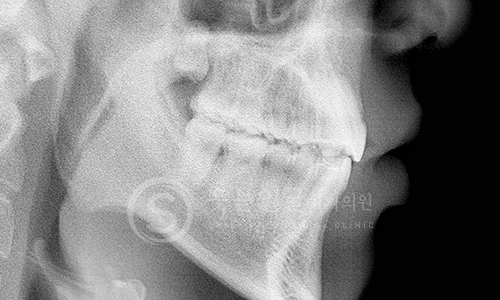

웃는얼굴치과의 12단계 교정진단시스템은 환자의 치아와 턱 구조,

얼굴 균형, 교합 상태 등을 체계적으로 분석하여

최적의 치료 계획을 수립하는 첨단 진단 프로세스입니다.

02 파노라마 촬영

03 세팔로 촬영

04 턱관절 검사

05 정면 X-ray 촬영